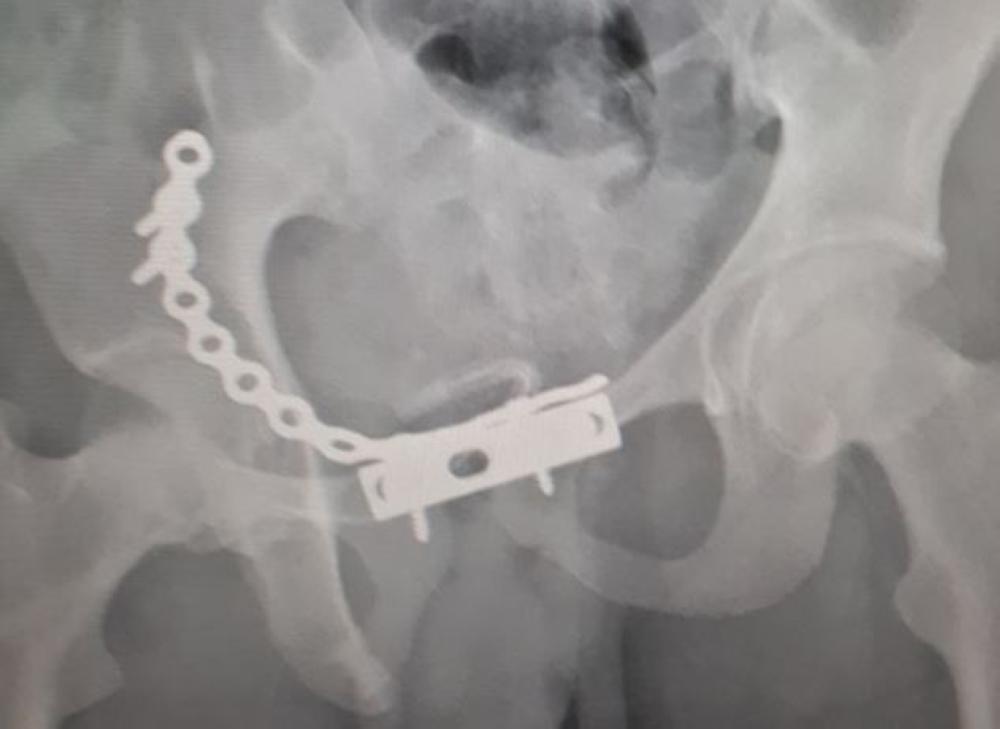

وقالت صحة الجوف: «المصاب تعرض لحادثة مرورية نتج عنها كسر بجسم الفقرة العنقية السادسة، وكدمات بالرئة اليمنى، وكسر بالجدار الأمامي المكون لعظمة مفصل الفخذ، وتوسع بعظام العانة، وخلع خلفي بالمفصل الأيمن، وبعد عرض الحالة على فريق طبي بالمستشفى قرر إجراء تدخل جراحي لرد الخلع المفصلي، وتوسع عظام العانة، وتثبيت الكسور بواسطة شرائح ومسامير معدنية خاصة لمثل هذه الكسور».